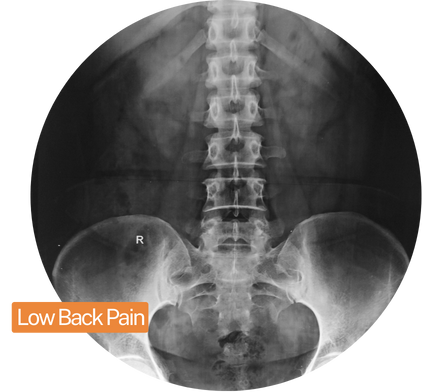

Low back pain, also known as lumbar pain, refers to discomfort or pain in the lower region of the spine, below the ribcage. It’s an extremely common condition, affecting nearly everyone at some point in their lives.

In fact, low back pain is one of the most frequent reasons for missed work worldwide. While it often resolves on its own, persistent pain may require medical intervention for effective treatment.